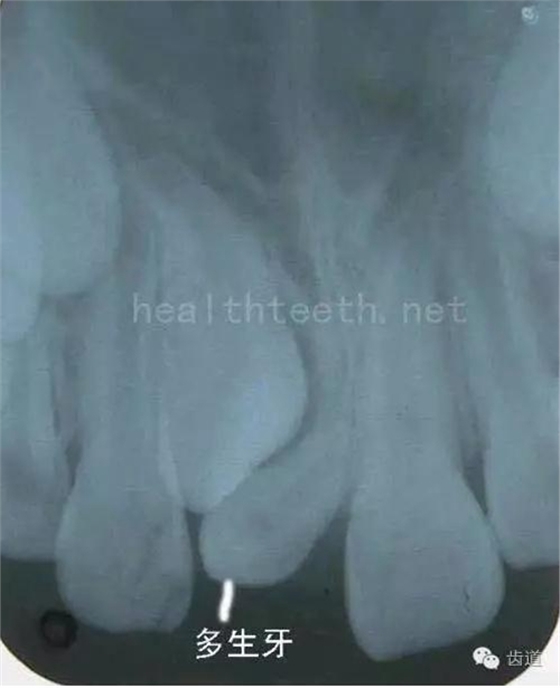

因?yàn)楸旧聿桓阏衬げ。占降牟±邢?,大多是同事收?/span> 頰粘膜扁平苔蘚 舌粘膜扁平苔蘚 舌緣創(chuàng)傷性潰瘍 長期戴活動義齒不當(dāng)或是戴不良修復(fù)義齒造成的口腔粘膜潰瘍,應(yīng)該引起高度警惕,因?yàn)檫@種潰瘍?nèi)菀装┳?/span> 黑毛舌 舌息肉,該患者同時伴有胃、食管息肉,后來看內(nèi)科了,具體情況不詳 四、孩子的牙齒問題 乳牙未退,牙根穿出牙齦對上唇粘膜造成刺激 乳牙滯留,也是孩子在退牙過程中最容易遇到的問題 五、牙齒發(fā)育上的問題 變色牙 氟斑牙 釉質(zhì)發(fā)育不全 四環(huán)素牙 牙神經(jīng)治療后的牙齒變色 10歲孩子剛剛萌出的牙齒變色 2、埋伏牙 左上乳3滯留,恒3未見萌出,曲面斷層片顯示牙齒埋伏 通過CT片確定埋伏牙齒具體的位置,顯示距離左側(cè)上頜竇很近,偏唇側(cè),這為手術(shù)定位提供了方便 手術(shù)中切斷、完整拔出,未損傷上頜竇 其他埋伏牙 3、多生牙 病例1 病例2 病例3,同時多生兩顆牙齒 4、各種畸形牙 畸形過小牙 融合牙:恒牙和乳牙都可以發(fā)生融合的情況(兩顆牙齒長在了一起) 畸形中央尖:在牙齒的中央,兩個牙尖之間又多長出一個牙尖,由于進(jìn)食的磨耗很容易造成磨穿,神經(jīng)就會與外界相通,出現(xiàn)牙髓炎的癥狀 六、牙齒的外傷 牙冠折斷 牙根折斷 烤瓷牙打樁修復(fù)后牙根折斷 外傷后牙齒的全脫位,應(yīng)該保留牙齒盡早做再植手術(shù) 七、牙齒的慢性損傷 牙頸部楔狀缺損 牙冠劈裂及完整拔除后的情況 牙根縱裂及拔除后的情況 牙隱裂,牙齒表面有肉眼看不到的裂紋,細(xì)菌通過其進(jìn)入牙髓,容易出現(xiàn)牙髓炎癥狀,嚴(yán)重可以造成牙齒的劈裂 這是一位來中國學(xué)習(xí)的俄羅斯大學(xué)生的牙齒,已經(jīng)做過了根管治療,牙齒咬合面有隱裂,通過鋼絲結(jié)扎固定,做鑄造金屬冠修復(fù)。 八、牙髓炎、根尖周炎 下面圖片都是慢性根尖周炎的病例,有了齲齒,進(jìn)一步發(fā)展就是牙髓炎,如果此時沒有得到及時的治療,疾病會逐漸發(fā)展破壞到根尖的骨質(zhì),將骨質(zhì)破壞后就在牙齦上出現(xiàn)一個膿瘺,此時患者不再感覺到牙齒的疼痛了,往往忽視了治療,但是這種不痛并不是疾病好轉(zhuǎn)了,而是因?yàn)榧膊〉难仔詽B出得到了引流,這個膿瘺會出現(xiàn)有時候變大了,有時候又變小了,但是如果不治療是不會自己愈合的,只有經(jīng)過完善的根管治療后才有好轉(zhuǎn)的可能,但是在疾病的治療中時間是起決定作用的,時間拖得越晚,好轉(zhuǎn)的可能性越小,經(jīng)過根管治療后如果膿瘺還是沒有消失,就需要做根尖刮治術(shù),如果仍然沒有好轉(zhuǎn),就只能做根尖切除術(shù)了,這對牙齒的穩(wěn)固是不利的。下面圖片中在膿瘺中插入了一個牙膠尖,是我們做根管充填用的材料,是非常軟的,就是在口腔牙齦瘺管的地方插進(jìn)去,通過拍牙片可以清晰地看到它到達(dá)的位置,從而確定發(fā)病的牙齒,此處是為了讓大家看得更清楚。 門牙兩個膿瘺 烤瓷牙修復(fù)后牙齦出現(xiàn)兩個膿瘺,插入牙膠尖,牙片顯示牙膠尖到達(dá)的位置就是根尖炎癥的位置,根尖骨質(zhì)密度降低(發(fā)黑的地方) 牙齒根尖膿瘺,治療前、中、后的圖片對照,完善根管治療后膿瘺明顯消失了 牙髓炎和根尖炎治療的關(guān)鍵就是根管治療 合格的根管充填治療 不良的根管充填治療 九、關(guān)于智齒(第八顆牙) 四顆長不出來的智齒 智齒反復(fù)發(fā)炎造成的頰瘺,膿腫切開引流后面部會留疤 智齒造成的頜骨囊腫,手術(shù)切除后需要植骨 十、各種錯合畸形 開合 深覆合 深覆蓋,上頜前突 反合(地包天) 牙齒排列擁擠 來源:牙醫(yī)愛看的 KQ88口腔醫(yī)學(xué)網(wǎng)